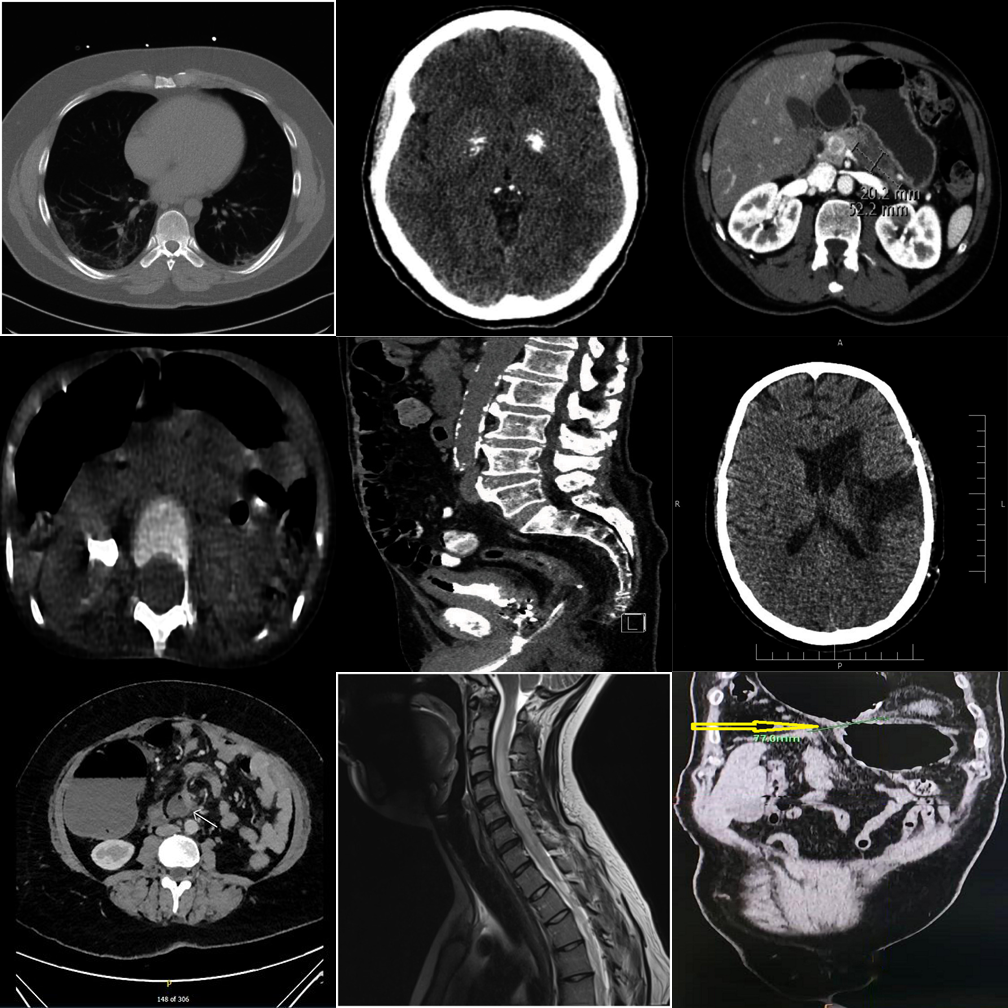

Anatomy and viewpoint mismatches. E.g., one abdomen CT among chest X-rays.

Referring MCQ gives a text hint about the anomaly type, making it easier to verify.

Cross-anatomy mismatches are easier when the anomaly type is described.

Referring MCQ typically achieves higher accuracy than detection protocols.

Open-ended generation reveals weaker grounding than constrained MCQ options.

Medical fine-tuning does not help — position bias dominates in open format.

Smallest proprietary model struggles with open-ended clinical reasoning.